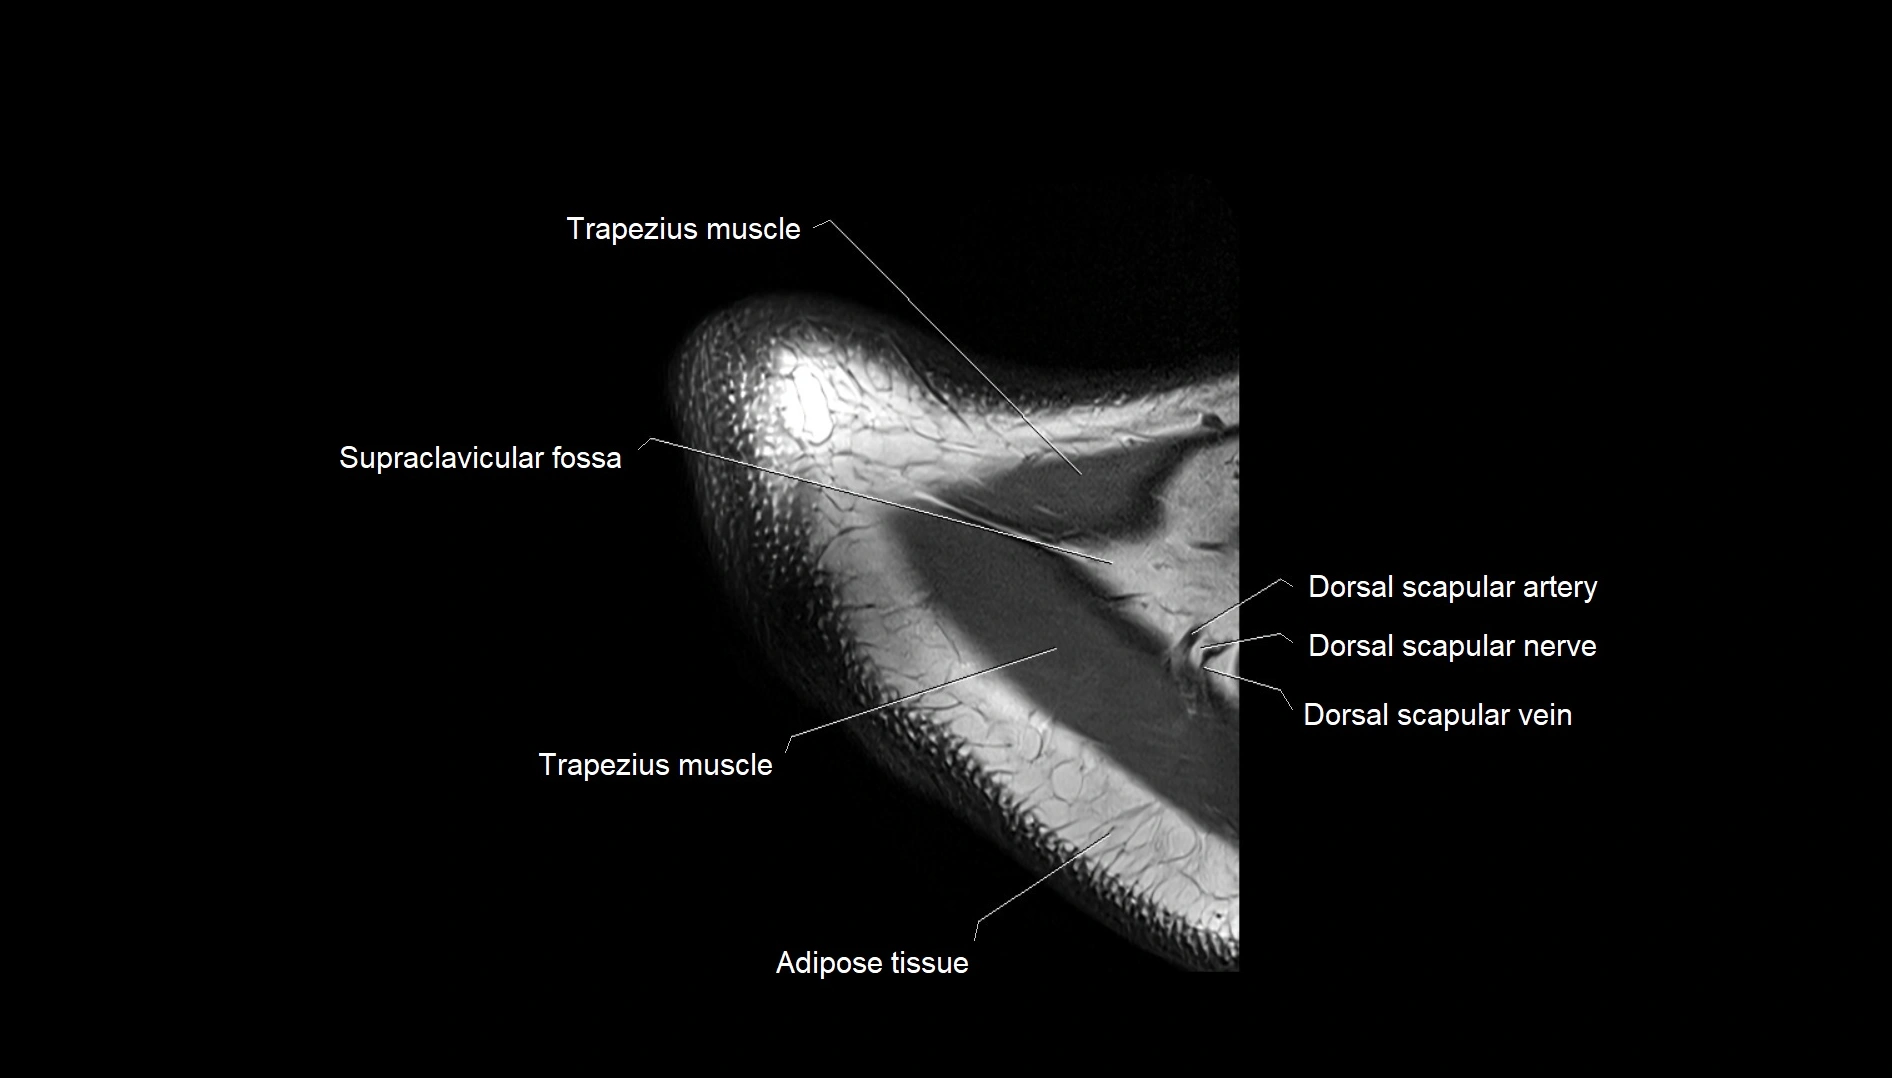

MRI images

image